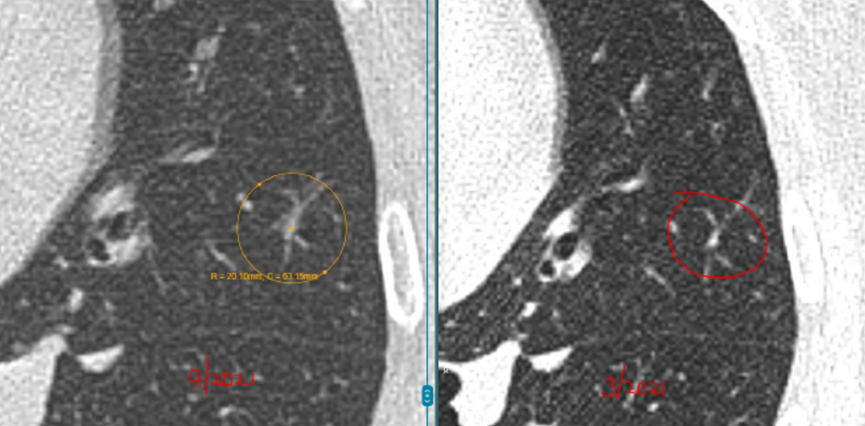

具体来看,右肺有一个磨玻璃结节(约4mm),左肺还有两个实性结节(约5mm、3mm)。

之后的4年里,这3枚小结节都没有什么变化,这让她逐渐放下心来。

然而在随后的一次复查中,CT结果显示磨玻璃结节“密度略微增加”,而且又新出现了一枚3mm的小结节。

关于右肺的4mm磨玻璃结节,L教授对比了新旧影像,并不认为它在恶化。

“这一枚,是您现在担心的,对吗?因为报告里提到它的密度比以前稍微高了一点。但从影像上看,这种变化还是非常轻微的,目前还没有达到让我们怀疑它正在明显恶化的程度。它确实值得继续随访,但至少以现在这个状态,还谈不上需要立刻处理,更不意味着已经朝着癌的方向快速发展。”L教授说。

关于右肺新出现的那枚大约3mm的磨玻璃结节,L教授同样为林女士进行了详细解释。

“像这么小、这么淡的磨玻璃结节,在临床上很常见,很多时候更像是一过性的炎性反应,可能和轻微感染甚至短期肺部状态变化有关。有些结节过一段时间复查,自己就消失了。所以对这枚结节,我目前更倾向于把它看作一个温和的、需要观察的信号,而不是一个必须马上干预的问题。”L教授说。

L教授总结道:“总体来看,您现在这4枚结节都还很小,而且没有哪一枚表现出必须马上手术或活检的证据。左肺两枚实性结节长期稳定,右肺原有的磨玻璃结节虽然密度略有变化,但幅度很小,新发的3mm磨玻璃结节也更像炎性改变。换句话说,它们都还没有到‘该切的时候’。现阶段继续按计划随访,是安全的,也是更合理的做法。”